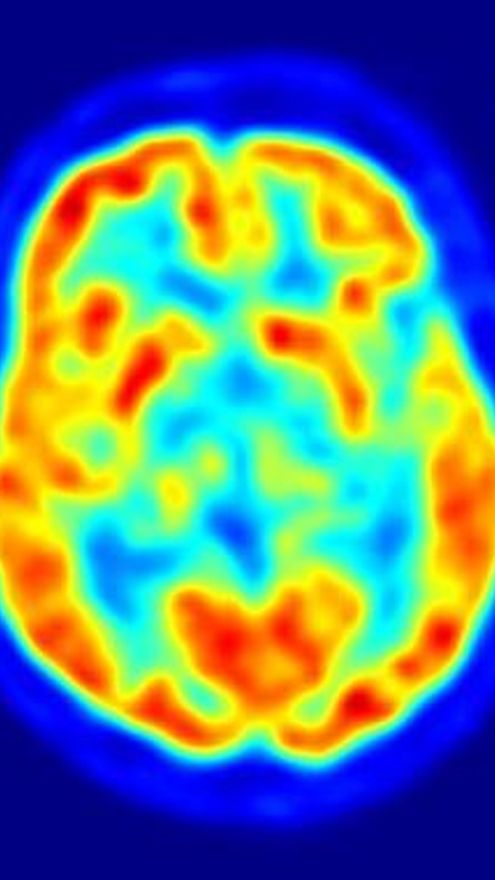

Entonces, los investigadores escanearon el cerebro de los voluntarios utilizando imagen por resonancia magnética funcional (fMRI, por sus siglas en inglés) mientras veían caras con expresiones de enfado, tristeza y neutralidad.

Así fueron capaces de medir cómo las diferentes regiones del cerebro reaccionaban y se comunicaban con otras cuando los voluntarios observaban caras de enfado, en contraposición a cuando lo que veían eran rostros tristes o neutrales.

Los resultados mostraron que los niveles bajos de serotonina hacen que la comunicación entre regiones específicas del cerebro del sistema límbico emocional --una estructura denominada amígdala-- y los lóbulos frontales más débil que cuando los niveles de serotonina son normales.

Utilizando un cuestionario de personalidad, los investigadores analizaron también cuáles de los voluntarios presentaban una tendencia natural a comportarse de manera agresiva. En estas personas, las comunicaciones entre la amígdala y el cortex prefrontal eran incluso más débiles tras la disminución de la serotonina.